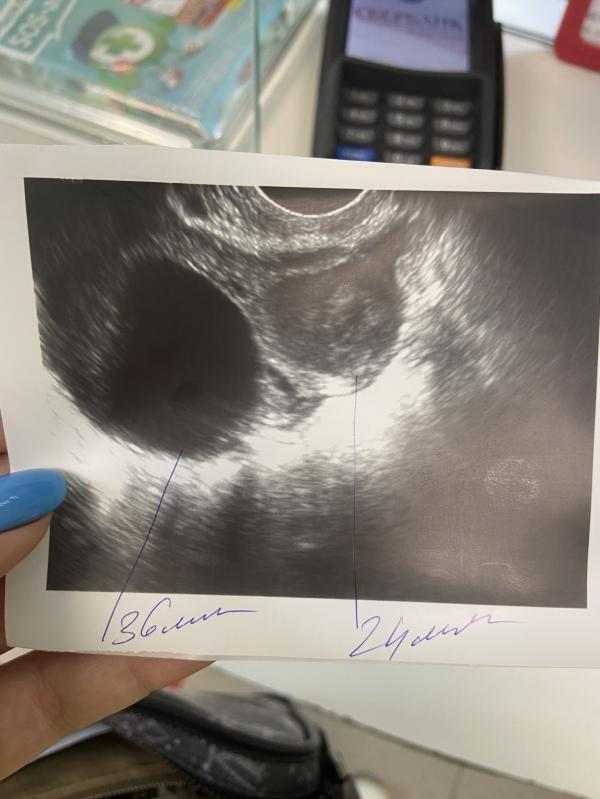

С лева киста 36 мм

С права желтое тело 24 мм